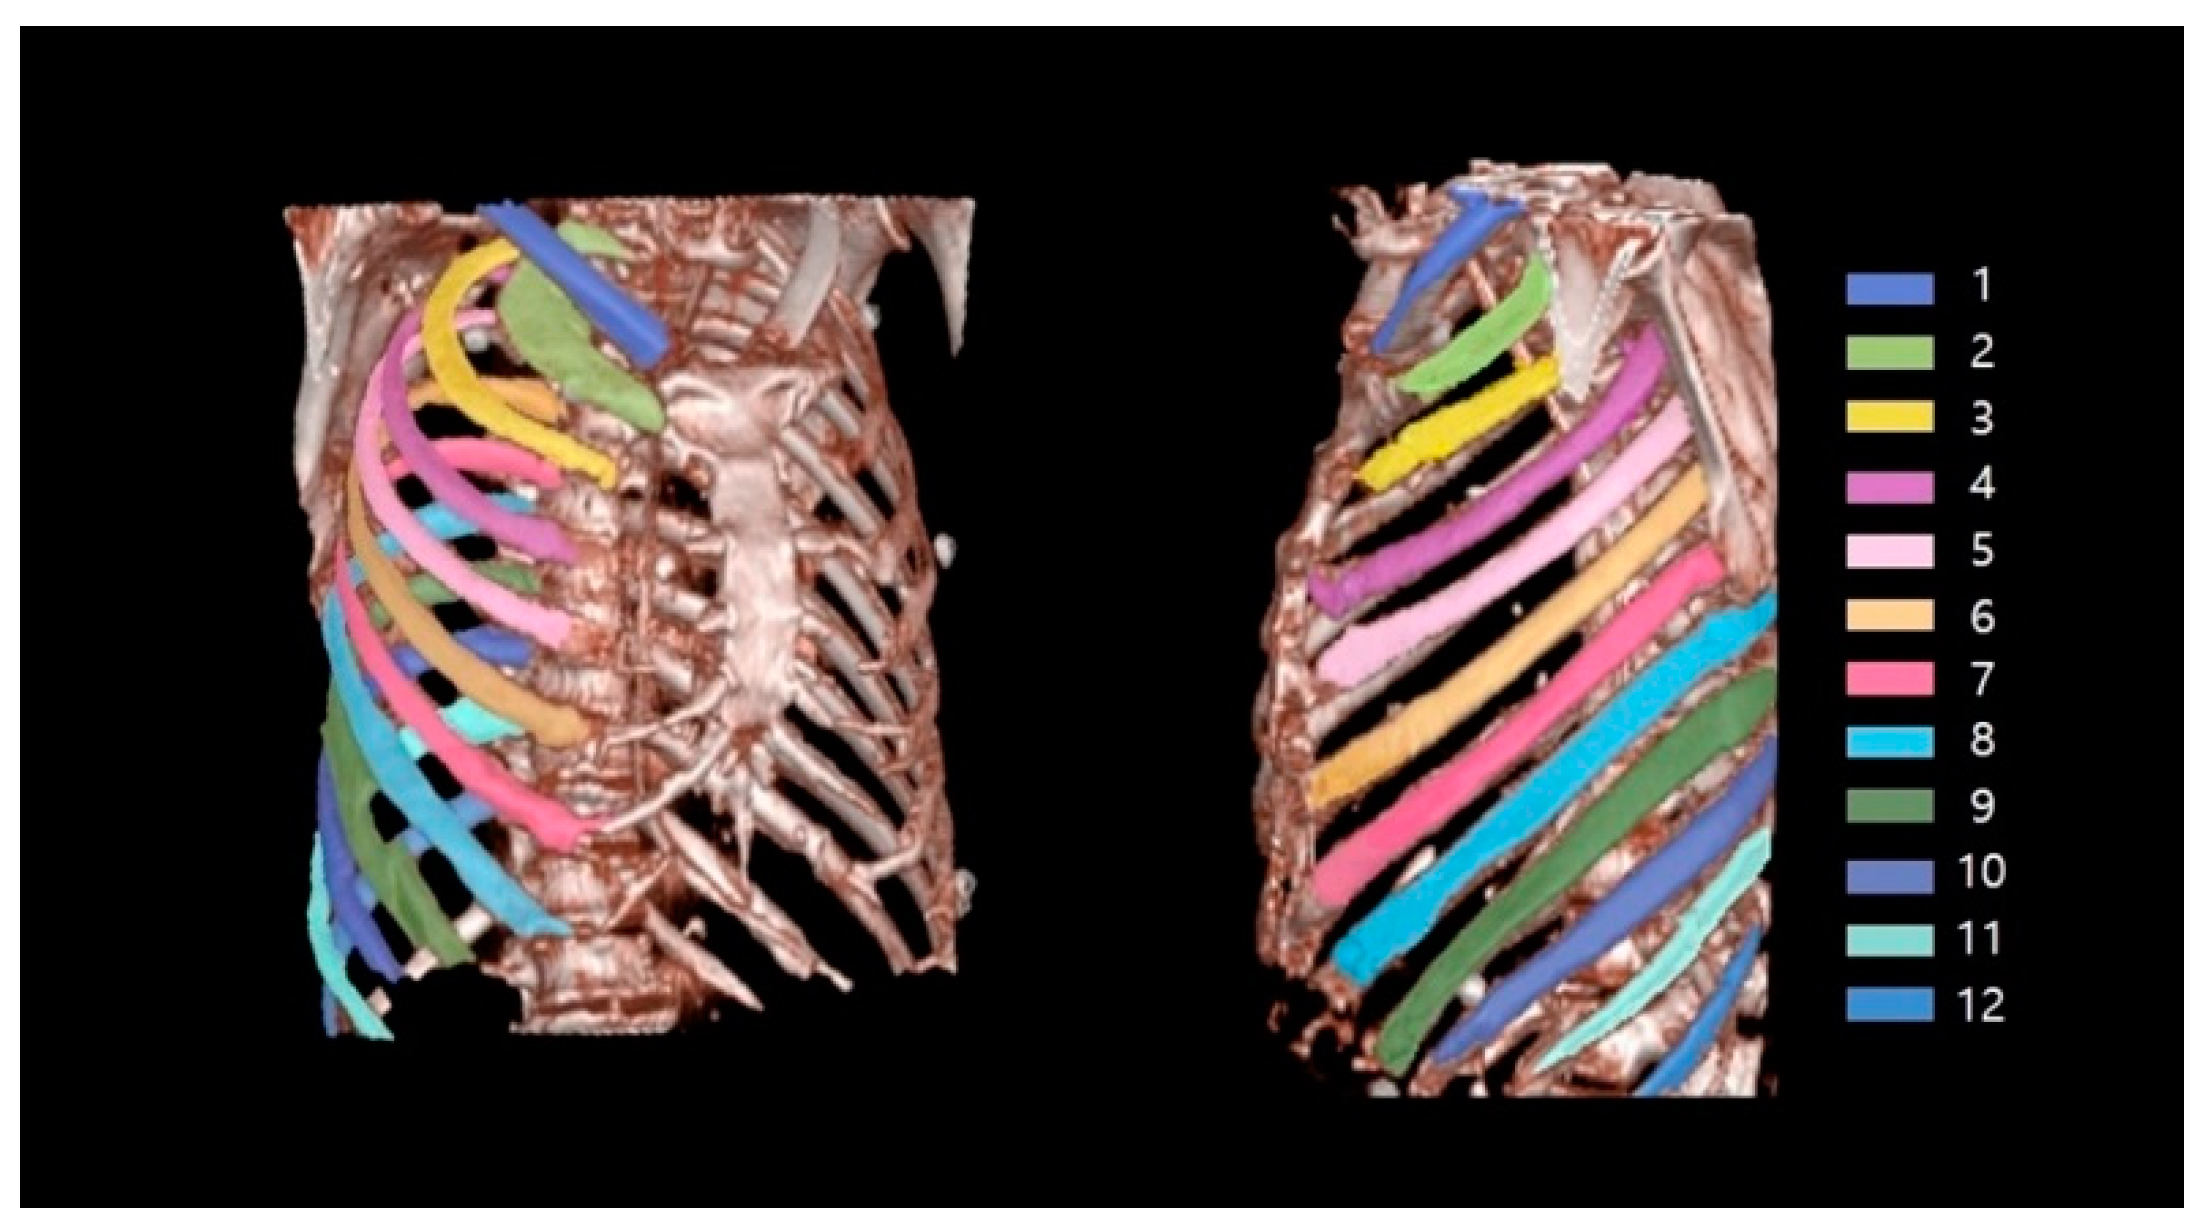

Figure 5 shows an example of successful automatic rib segmentation and sequence labeling (Figure 5). Intuitive results are displayed via colored labels and boxes in Figure 5. In addition, the result of sequence labeling is reconstructed on 3D rendering models with color annotations to verify the performance of the developed system (Figure 6).

Figure 6.

Verified results of sequence labeling on 3D-rendering rib models with colored annotations.